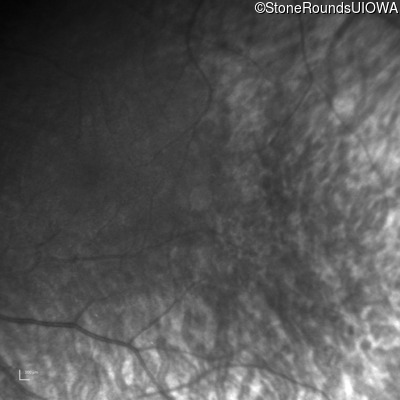

Infrared Fundus Photograph - Right -

No Light Perception

Exemplar

Infrared Fundus Photograph - Left -